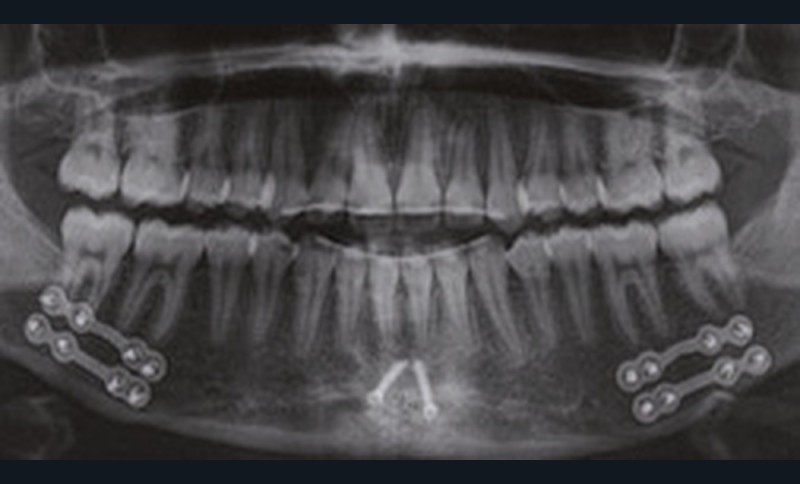

À la vue de l’examen radiographique, elle est au stade CS6 d’après la méthode de maturation vertébrale de Baccetti [1]. Elle présente une classe II squelettique de Ballard par rétrognathie mandibulaire avec un ANB de 9° et un AoBo de 9 mm sur un schéma facial normo-divergent. L’incisive mandibulaire est vestibulo-versée (IMPA = 114°). Le maxillaire est bien positionné. Elle présente de plus une dysharmonie dento-dentaire (DDD) antérieure par excès mandibulaire.

Nous équipons la patiente avec un appareil multi-attaches (.022 x .028 inch pré-informé Roth) mais nous n’avons pas activé l’arcade mandibulaire. La patiente est adressée au chirurgien maxillo-facial (Dr Gonzague Deffrennes, hôpital Beaujon) qui réalise l’avulsion des troisièmes molaires et la pose de plaques vissées avec émergence entre les premières et deuxièmes molaires mandibulaires dans l’axe des brackets (fig. 9). Étant donné l’absence d’encombrement au niveau incisif mandibulaire, nous pouvons rapidement mettre en place les tractions postérieures. Nous solidarisons ainsi le bloc antérieur de canine à canine et réalisons un recul en masse de l’arcade directement des canines aux plaques postérieures. La majeure partie du recul est faite sur un arc acier .018x.025 inch permettant le glissement. La force appliquée est de 250-300 g par côté.

Nous avons pu repositionner l’incisive mandibulaire de 8° (fig. 10), obtenir un surplomb correspondant à la classe II d’Angle et ainsi réaliser l’avancée mandibulaire. Le chirurgien accompagne celle-ci d’une génioplastie afin d’harmoniser le profil. Nous corrigeons la DDD par stripping des incisives mandibulaires ce qui permet de corriger encore de 1° l’axe incisif.